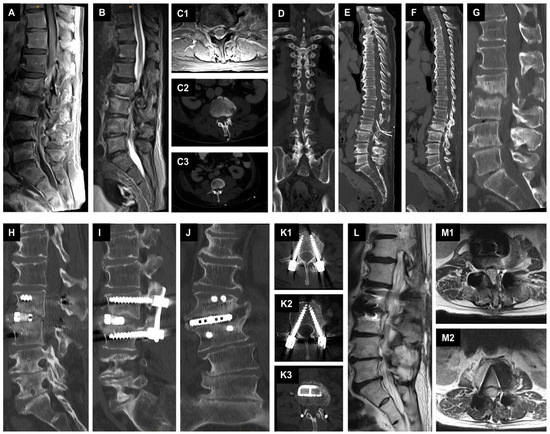

2.3.1. First Case with Isolated Spinal Epidural Empyema

2.3.2. Second Case with Spondylodiscitis and Epidural Empyema